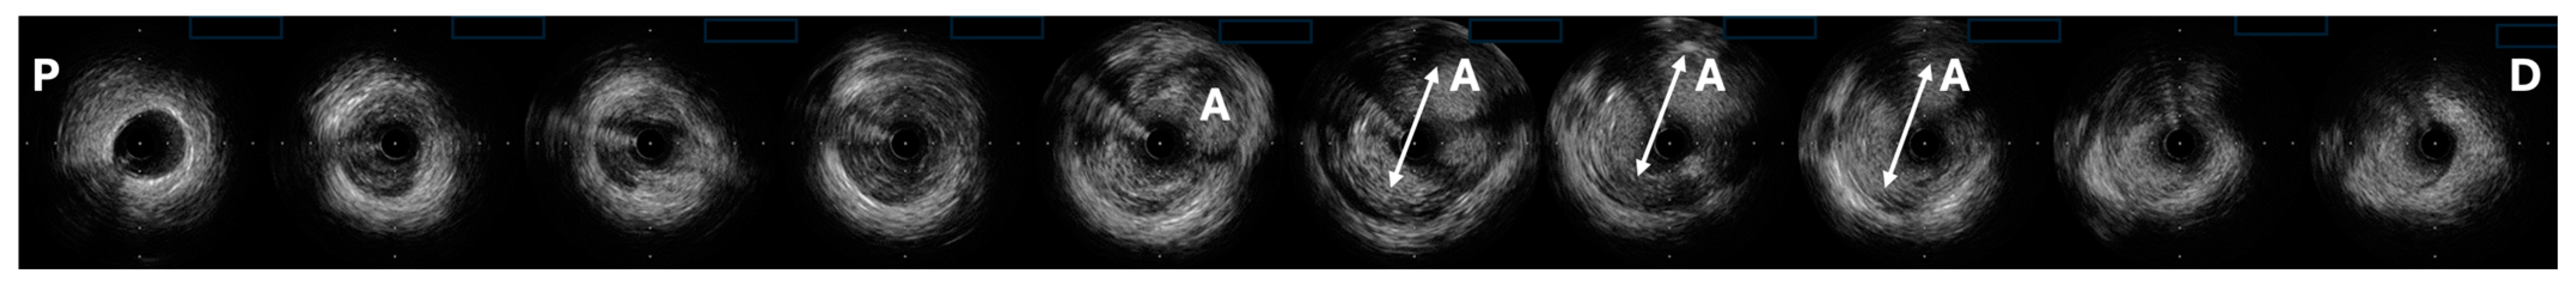

4. Diagnostics